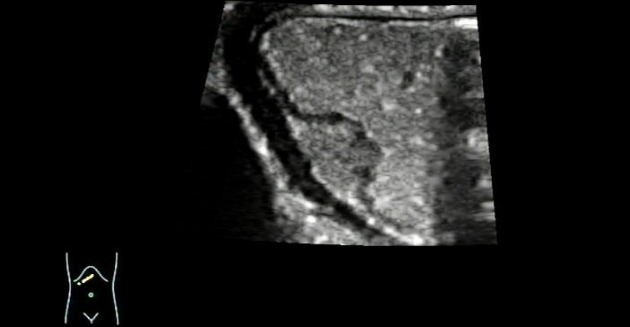

??? ???(instant gastrointestinal ultrasound aid) 500mL? ?? ???? ?? ? ??? ??? ?????. Gastric wall? ??? ???? ?? ??? ???? ?? ??????, Gastric antrum? lesser curvature? submucosal layer??? ? 1.36cm├Ś0.87cm ??? ?? ??? hypoechoic mass? ???????. ??mass? ????? ????? ????, ???? ?? ???? ???????.

???, mass? ??? ???? ?? ??? ?????, mass ????? ???? echogenicity ? ???????.(?? 3).